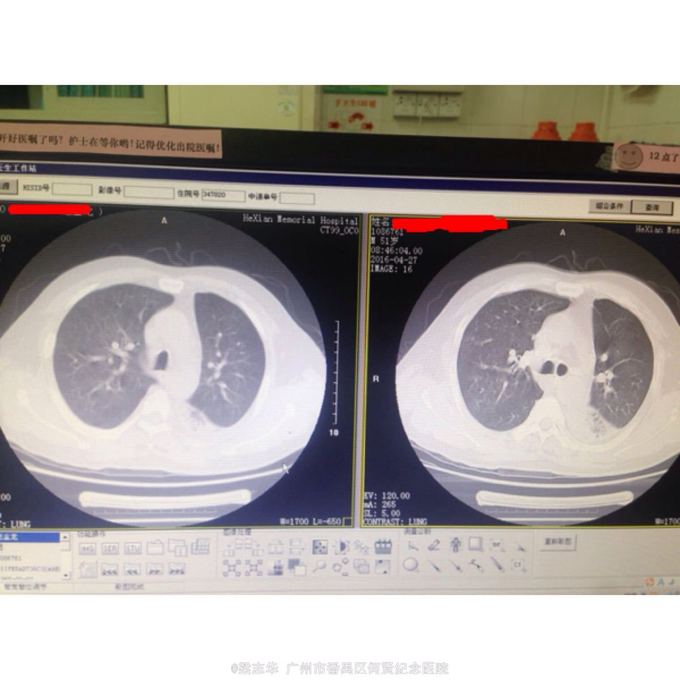

体查:T:36.8℃ R: 20次/分 P:110次/分 BP:130/76mmHg,全身浅表淋巴结未扪及肿大,胸廓对称无畸形、无局部膨隆或凹陷。呼吸平稳,节律规则。双侧呼吸动度对称。双肺部叩诊清音。左下肺呼吸音低,左下肺可闻及较多痰鸣音。心界不大,心率110次/分,律齐,各瓣膜区未闻及病理性杂音。 辅助检查:2016-04-23 血常规:WBC-LE 17.7 10^9/L ↑ NEUT#-LE 14.75 10^9/L ↑ NEUT%-LE 83.2 % ↑ KS-CRP >200 mg/L ↑ 。2016-04-24 ESR 98.0 mm/h ↑ 。2016-04-27 HBA1C 6.1 % ↑ 。双肺CT:1、右肺中叶及左肺上叶舌段、下叶支气管扩张并感染;左肺下叶多发空洞,考虑肺脓肿;右肺中叶肺不张、左肺下叶膨胀不全。2、左侧少量胸腔积液。3、双侧胸膜增厚、粘连。4、轻度脂肪肝。入院后血糖在5.6~9.3mmol/h。

诊断: 1.肺炎伴肺脓肿. 治疗:入院后予吸氧抗炎(莫西沙星)化痰等治疗,并行左侧胸腔穿刺术,但术中未能抽出脓液,经上述治疗,患者症状好转,体温逐渐下降。